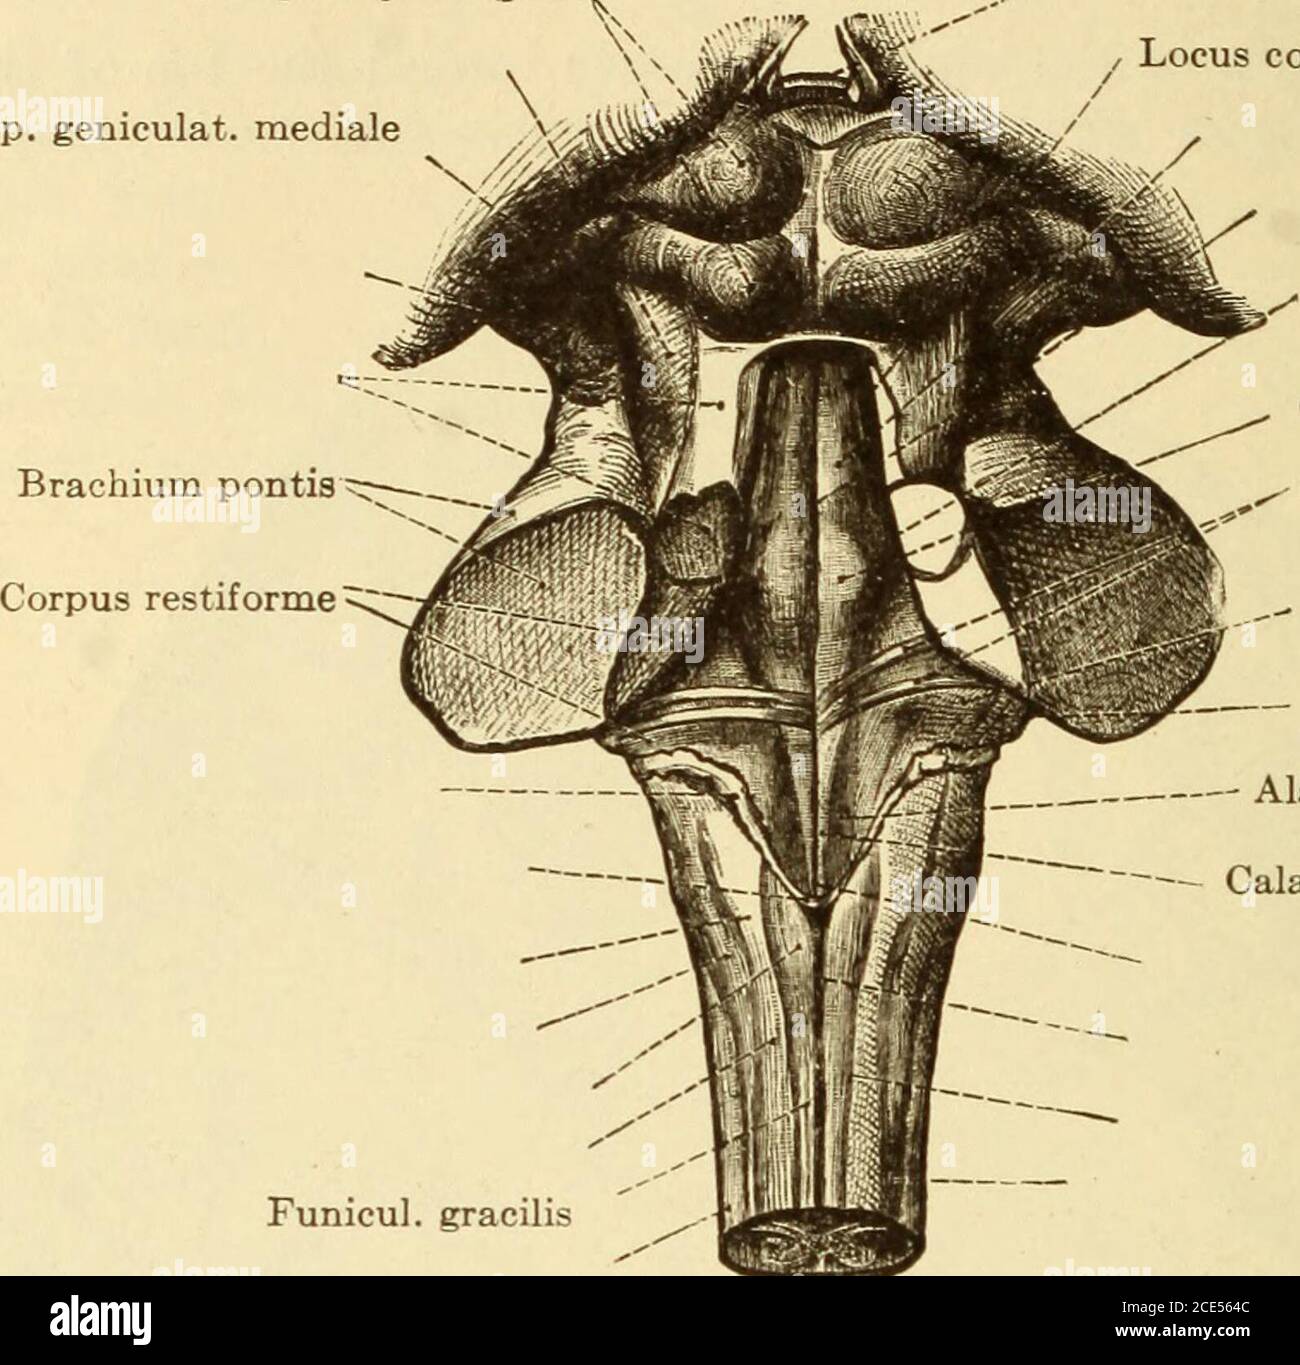

RM2CE564C–. Erkrankungen des Nervensystems . Abb. 43. – Basis der Braix axd Hirnnerven. Sucht nach ihren Hauptabteilungen im Menschen, der Korpora quadrigemina (siehe Abb. 44und 45) oben die Spalte von Sylvius unten, und darunter die Fasermasse der oberen Pedunkles des Kleinhirns und der Pedunculi cerebri (Abb. 46, 47, 48, 49). Seine Kerne (Neuronenzellen) liegen entlang der gesamten Länge des Aquädukts von Sylvius, von seinem frontalen Ursprung fast bis zu seinem kaudalen Ende;5 52 HISTOLOGIE DES ZENTRALNERVENSYSTEMS die Kerne der trochlearen Nerven liegen posteriorly dort, wo der aque-Ductus liegt

RM2AWH2Y3–Die Anatomie des Nervensystems, vom Standpunkt der Entwicklung und Funktion. Die Fasern des Nervus facialis Bendum den Zellkern der Entführten. Der Locus 121, DER AUS pigmentednerven Nervenzellen besteht, erstreckt sich von der Fovea Superior bis zur Thecerebral Aquädukt ist eine flache, meist blassblaue Nut, darunter liegt die substantia ferruginea. Beginnend mit dem zerebralen Aquädukt und durch das superiorale und das inferiore Fovea? Ist eine sehr wichtige Nut, der Sulcus limitans, der die Trennlinie zwischen den von t abgeleiteten Teilen wieder aufsaugt

RM2CHEGP9–. Das Nervensystem: Ein elementares Handbuch der Anatomie und Physiologie des Nervensystems für den Einsatz von Studenten der Psychologie und Neurologie. Diese Nut der dritten Hirnnerven entstehen. Wo die Krura an die Ponen anschließt, liegen sie nahe beieinander, aber wenn sie vorwärts gehen, divergieren sie, so dass ein dreieckiger interpedukulärer Raum. Innere Struktur. - in einem transversem Abschnitt über die Mitte des Gehirns kann das Aquädukt von Sylvius in der Nähe der überlegenen Oberfläche (Abb. L 56, S. Graue Materie. - die wichtigen Massen der grauen Materie dieser Region vielleicht in vier Gruppen angeordnet : (1) die graue Materie surroun